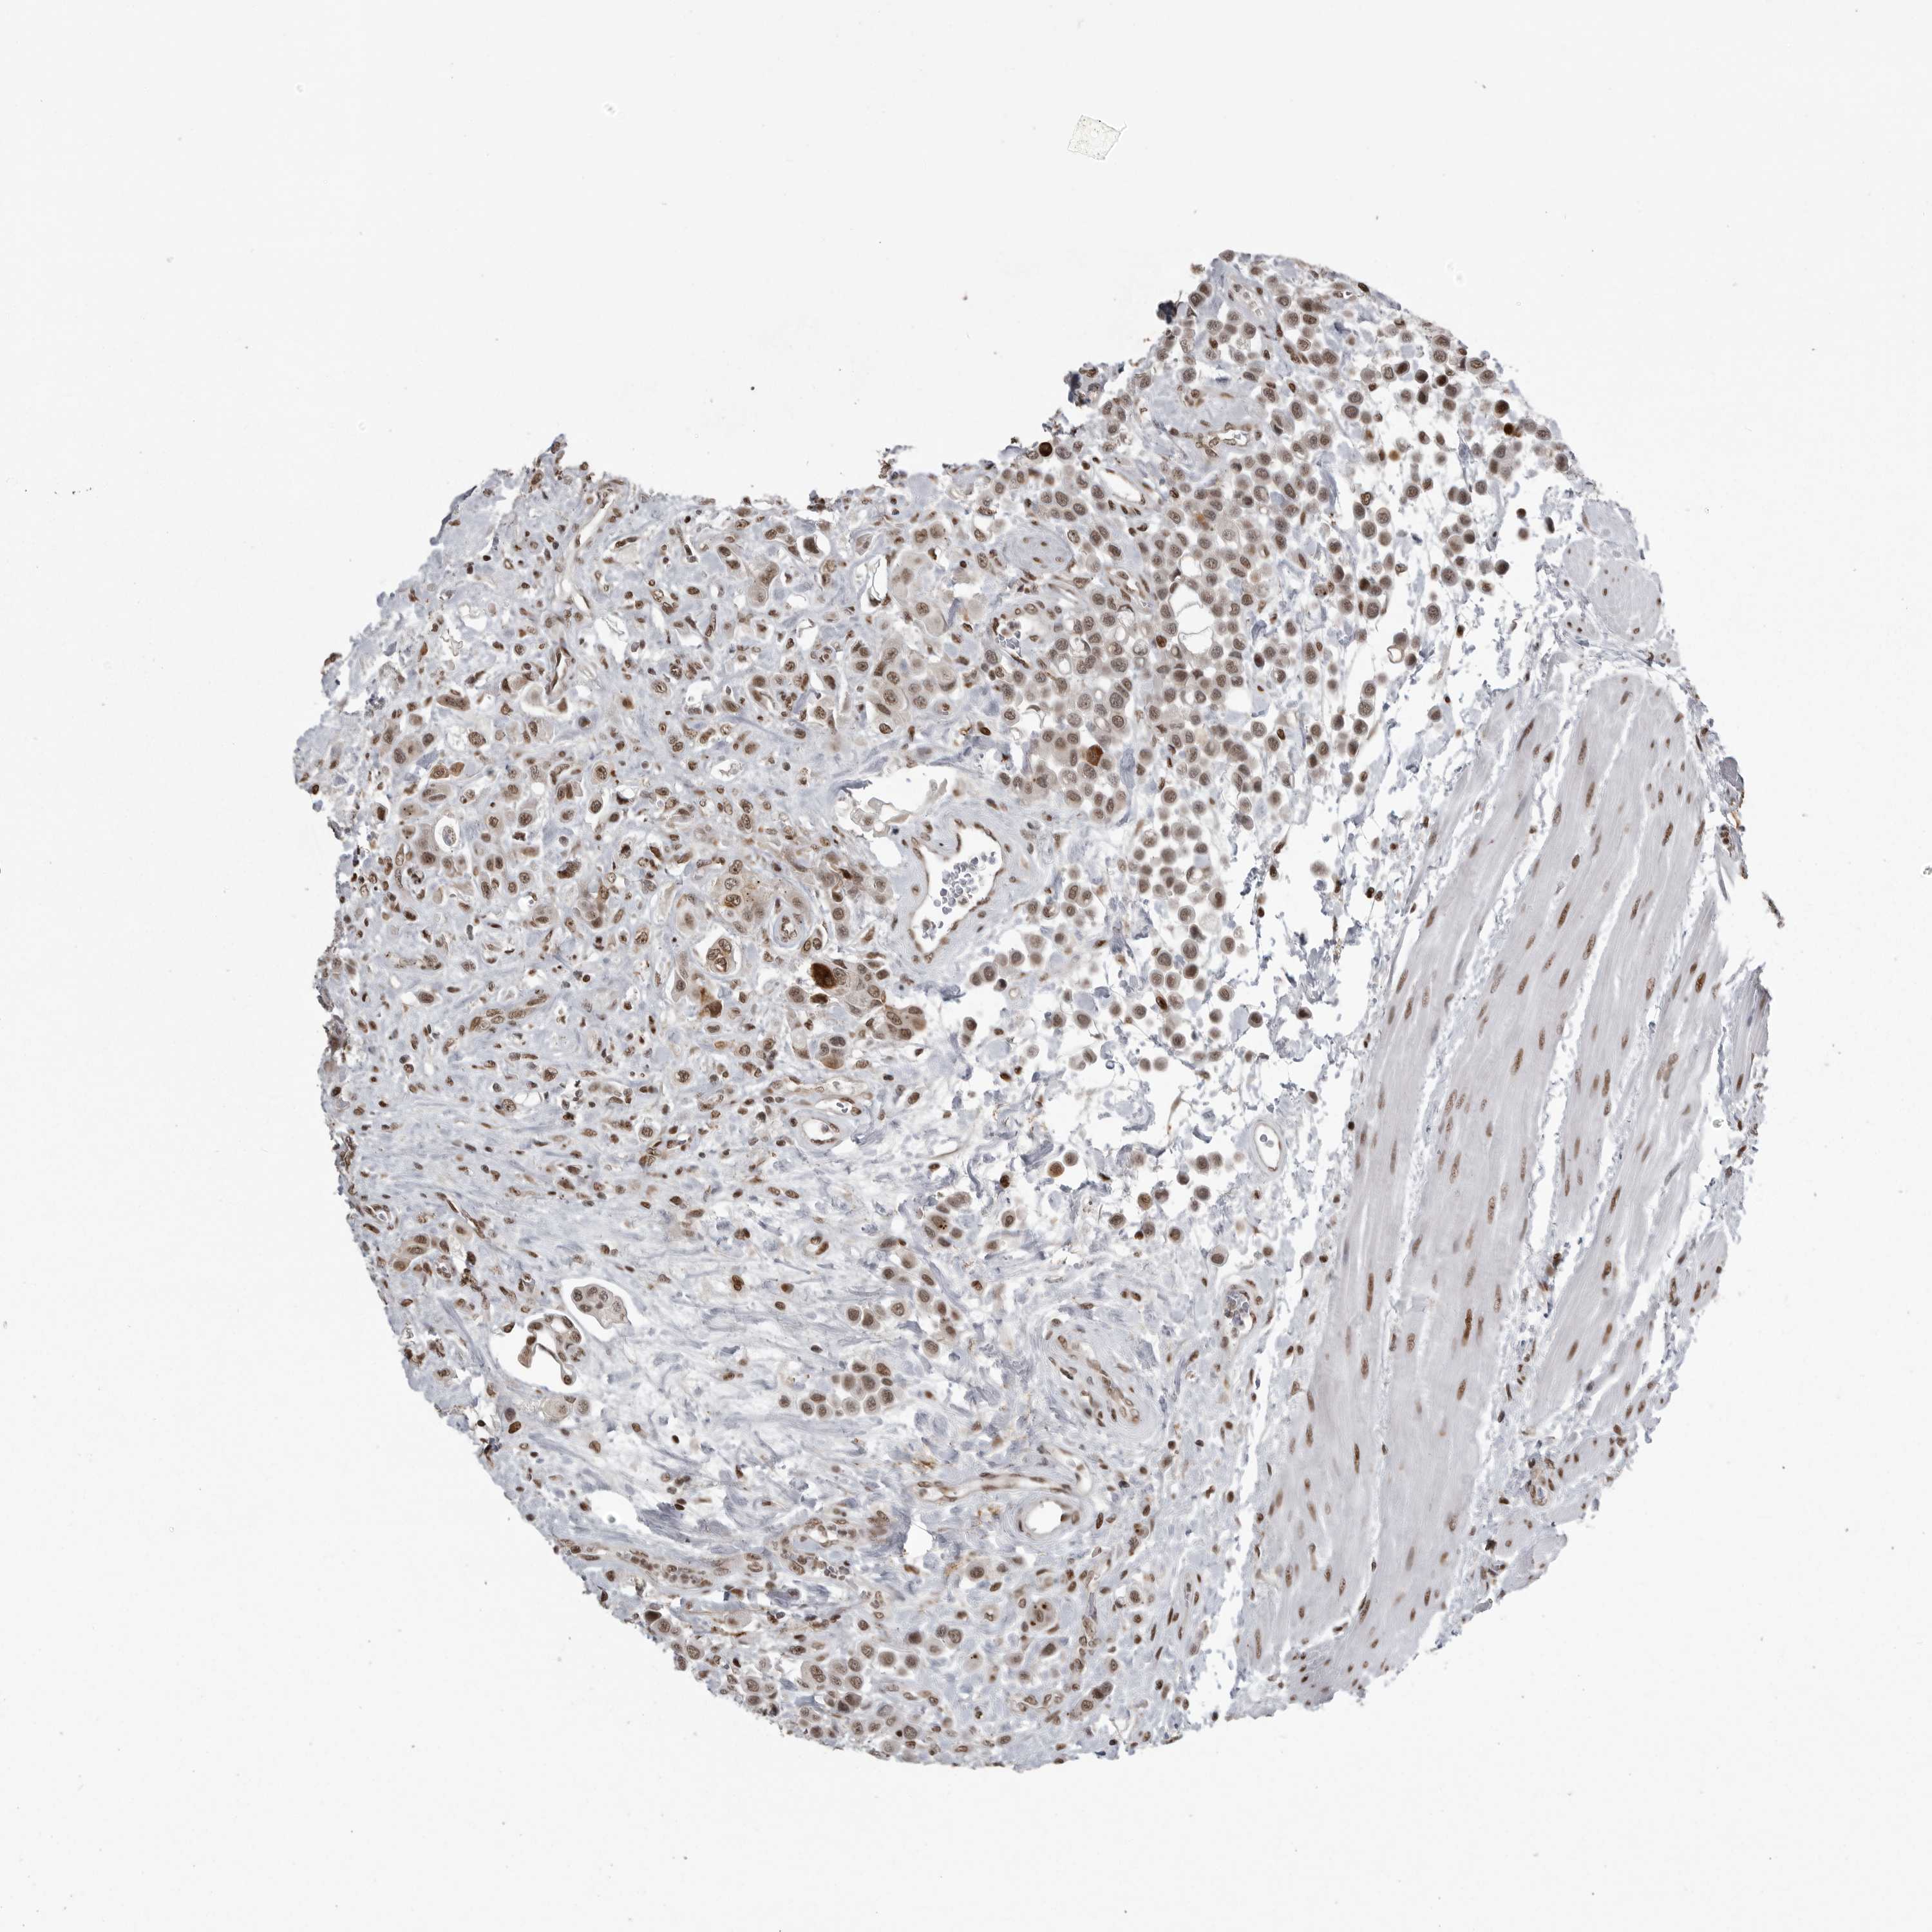

UROTHELIAL CANCER - Protein expressioni

A mouse-over function shows sample information and annotation data. Click on an image to view it in a full screen mode. Samples can be filtered based on level of antibody staining by selecting one or several of the following categories: high, medium, low and not detected. The assay and annotation is described here.

Antibody stainingi

Antibody staining in the annotated cell types in the current human tissue is reported as not detected, low, medium, or high, based on conventional immunohistochemistry profiling in selected tissues. This score is based on the combination of the staining intensity and fraction of stained cells.

Each image is clickable and will lead to virtual microscopy that enables deeper exploration of all samples and also displays staining intensity scores, fraction scores and subcellular localization as well as patient and tissue information for each sample.

Antibody HPA026867

Staining

High

Medium

Low

Not detected

Intensity

Strong

Moderate

Weak

Negative

Quantity

>75%

75%-25%

<25%

None

Location

Nuclear

Cytoplasmic/membranous

Cytoplasmic/membranous,nuclear

Urothelial carcinoma, Low grade

Urothelial carcinoma, High grade